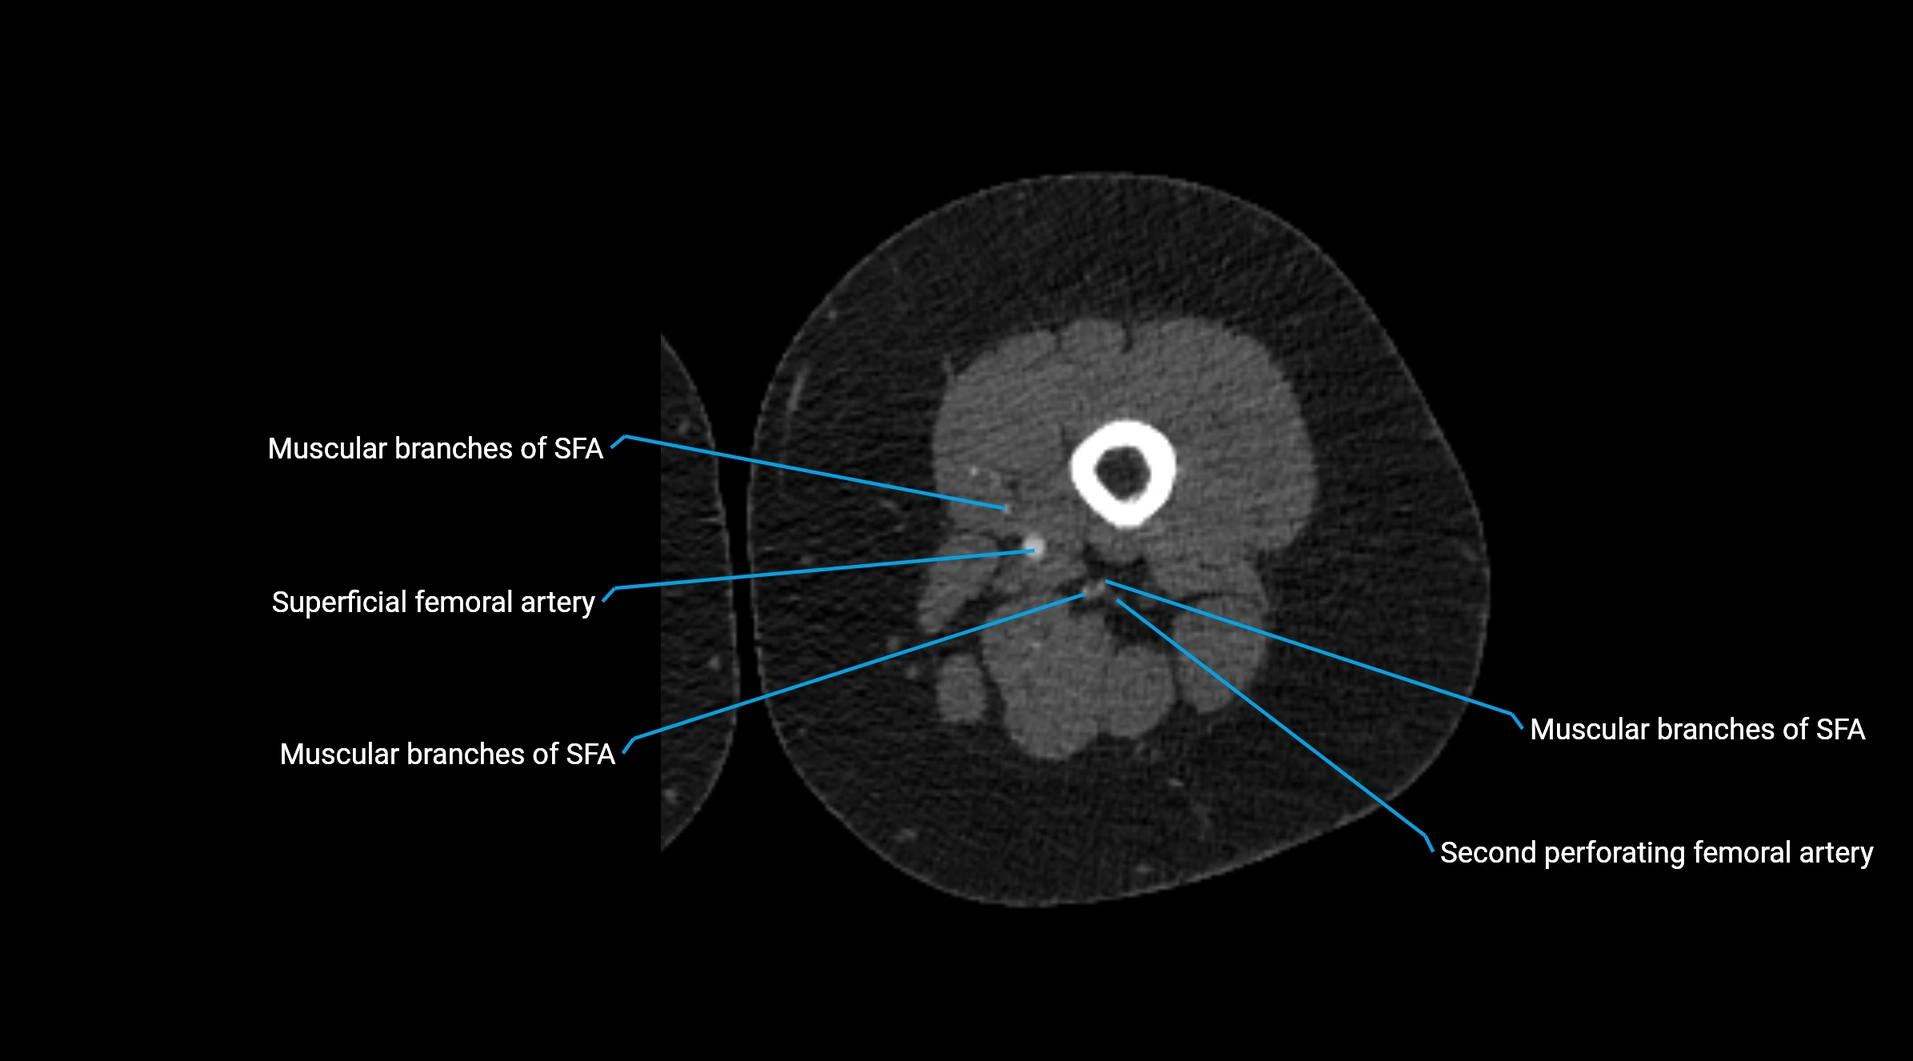

CT images

image